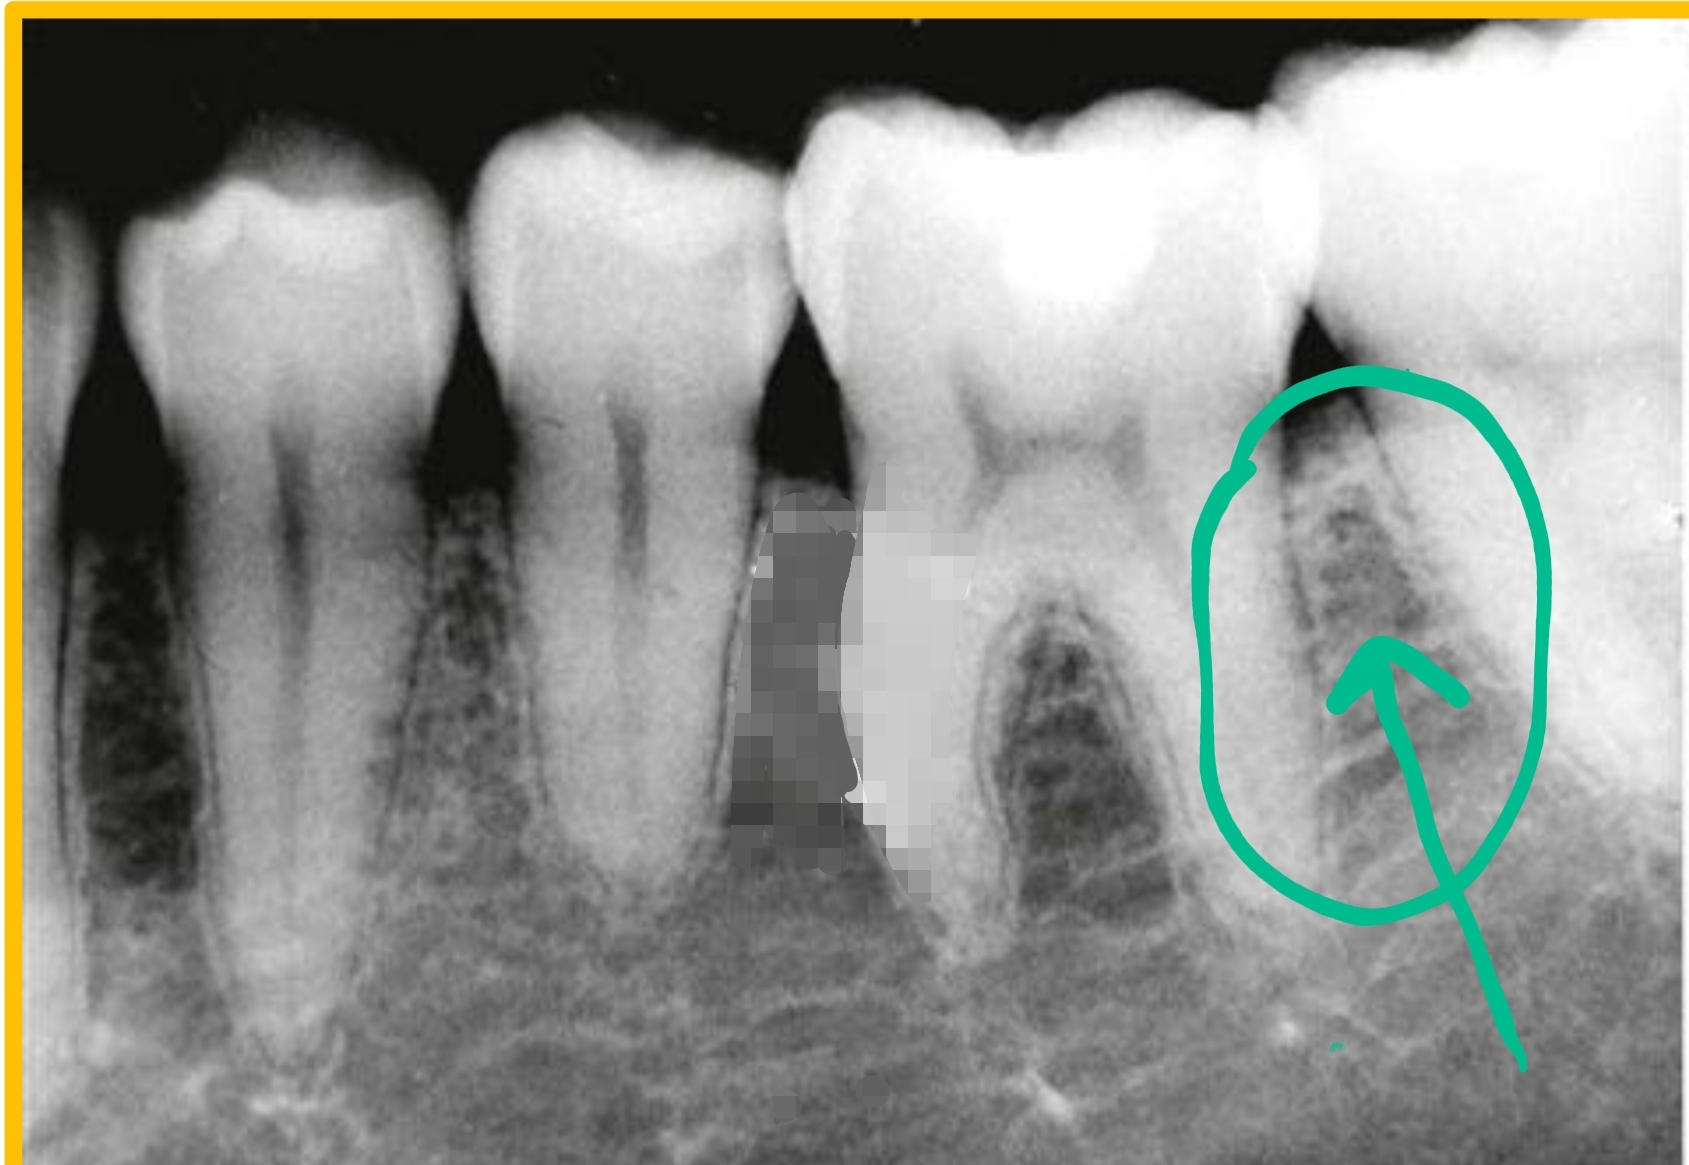

located between roots

Interradicular bone

located between teeth

Interseptal bone